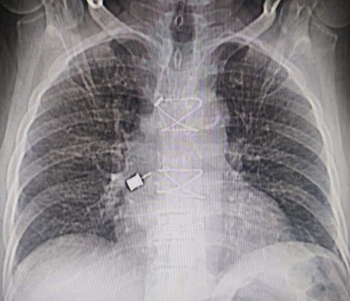

CT chest with thoracic angiogram revealed bilateral cavitary lesion with hypertrophied collateral arteries predominantly supplying the right upper lobe cavity. FOB done showed active bleeding from right upper lobe bronchus.

Watanabe sphigot occlusion of anterior subsegment of right upper lobe + glue instillation of right apical and posterior sub segment followed by bronchial artery embolization was done.

Pre procedure CT Scan

Pre procedure X ray

CT thoracic angiograph